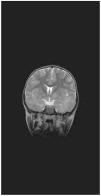

Se presenta el caso de un varón de 5 años, sin antecedentes de interés que, en el contexto de un síndrome mononucleósico por virus Epstein-Barr (VEB) (serologías IgM anti-VCA (antígeno de la cápside viral) y Paul Bunnell positivas, IgM anti-CMV (citomegalovirus) débilmente positiva), sufre una encefalomielitis aguda. El paciente ingresa con clínica de mononucleosis y deshidratación leve, en la segunda semana de evolución. Durante el ingreso sufre una crisis generalizada de hipotonía de 10min de duración. Se realizan pruebas complementarias: TC craneal, fondo de ojo y punción lumbar (que son normales) y EEG con asimetría interhemisférica, actividad paroxística focal parietotemporal bilateral y enlentecimiento en el hemisferio derecho. Ante la sospecha clínica de meningoencefalitis primaria se inició tratamiento intravenoso con ganciclovir, cefotaxima y fenitoina. Tras 48h de mejoría se observa un empeoramiento con encefalopatía (Glasgow oscilante: 9–12), ataxia, afasia, arreflexia y vejiga neurógena. Se repite la TC, en la que se observa edema vasogénico con efecto masa, de predominio temporal izquierdo con isquemia de globo pálido. Ante la sospecha clínica de encefalomielitis aguda, se inicia tratamiento con metilprednisolona IV (30mg/kg/día) y gammaglobulina IV (500mg/kg/día durante 5 días), con mejoría sintomática en días posteriores. Se mantiene ganciclovir hasta la recepción del resultado de la reacción en cadena de la polimerasa (PCR) para virus neurotropos, con negatividad de VEB y CMV en líquido cefalorraquídeo (LCR). El cuadro de encefalomielitis aguda diseminada (EMAD) se confirma mediante una resonancia magnética nuclear (RMN), en la que se observa lesión difusa de la sustancia blanca supratentorial e infratentorial, asimétrica, de predominio parietotemporal izquierdo y en el tegmento protuberancial, con aumento de su señal en secuencias T2 y FLAIR (figs. 1 y 2). Presenta una mejoría clínica progresiva y al alta, a las 4 semanas, la exploración neurológica es normal. Se mantiene pauta corticoidea descendente hasta 6 semanas, asociada a valproico (VPA). A los 3 meses, en el EEG persiste actividad lenta de predominio temporal y se continúa el tratamiento con VPA. A los 10 meses, las imágenes de RMN de control son normales, el niño permanece asintomático y se inicia descenso progresivo del VPA.